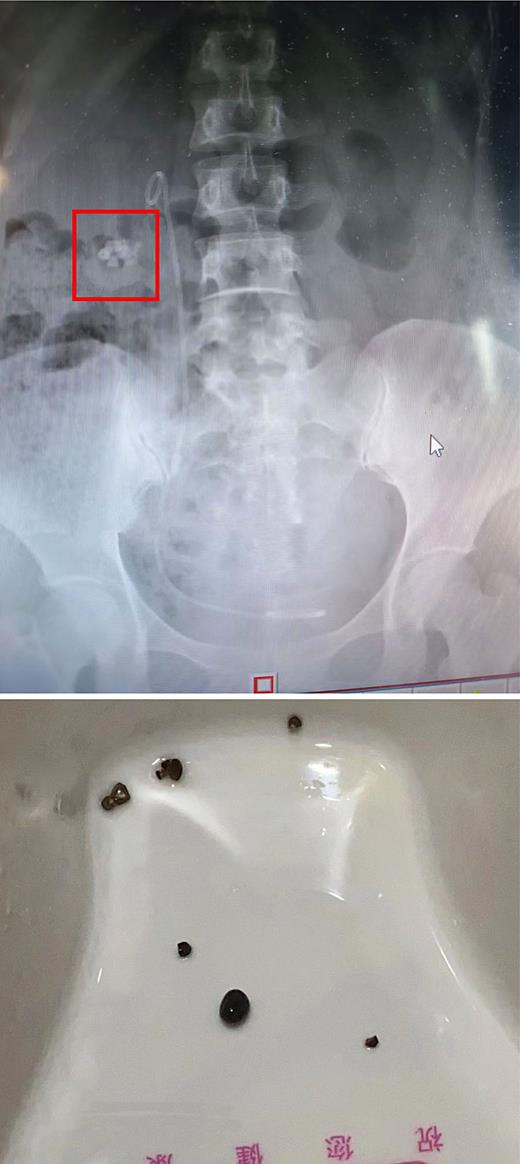

The image above shows the RF position of the urinary tract radiograph; the image below shows RF excreted in urine after four EPVL sessions.